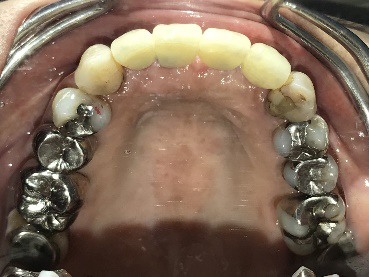

男性Kさん 50代(インプラント)

歯がグラグラするところ、むし歯のところ、しみるところ、被せ物がとれたところ、歯茎が腫れて血が出るところ、歯が抜けているところがある。すべて治したい。

治療内容

残っている歯を抜歯し、上下インプラント治療をしました。

所感

歯周病が進行している歯、むし歯が進行している歯がほとんどで、レントゲンを撮り、詳しく診てみると、ほとんどの歯を保存することができないことがわかりました。抜歯後は、入れ歯かインプラントの方法があります。治療開始前に患者さんに詳しく現状を説明し、治療法についてじっくり相談しました。自分の歯と同じような感覚で食事できるインプラント治療を選択されました。治療後、表情がとても明るくなり、口元がとても自然で10歳以上若返ったように感じました。「時間はかかりましたが、インプラントにして本当に良かったです!」と素晴らしい笑顔でお話ししてくださいました。

上顎:¥3,280,000(税込)

下顎:¥3,280,000(税込)